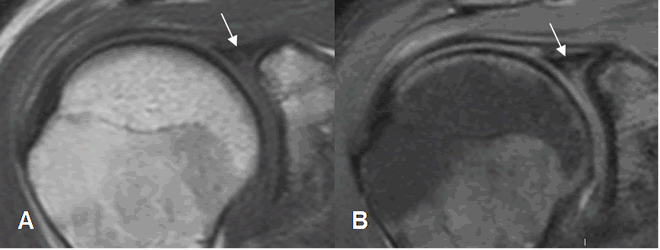

Fig 74. Lesión SLAP.

A: RM coronal en T1 y B: RM coronal en STIR. Imagen hiperintensa y en sentido oblicuo sobre el labrum superior, por lesión SLAP.